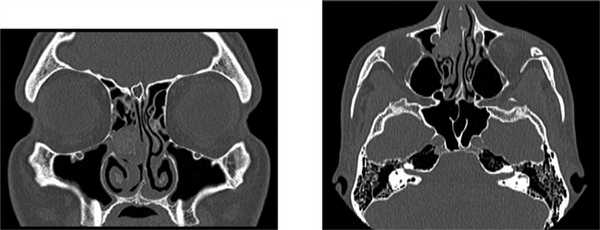

По данным мультиспиральной компьютерной томографии носа и околоносовых пазух: в полости носа справа, в области среднего носового хода, выявляется новообразование размером 16,5×15,5 мм, полностью обтурирующее просвет среднего носового хода и исходящее, вероятно, из средней носовой раковины. Целостность костных структур не нарушена (см. рисунок). Пациент Б., 34 лет. МСКТ носа и ОНП. Patient B., 34-year. MSCT of the nasal cavity and paranasal sinuses.